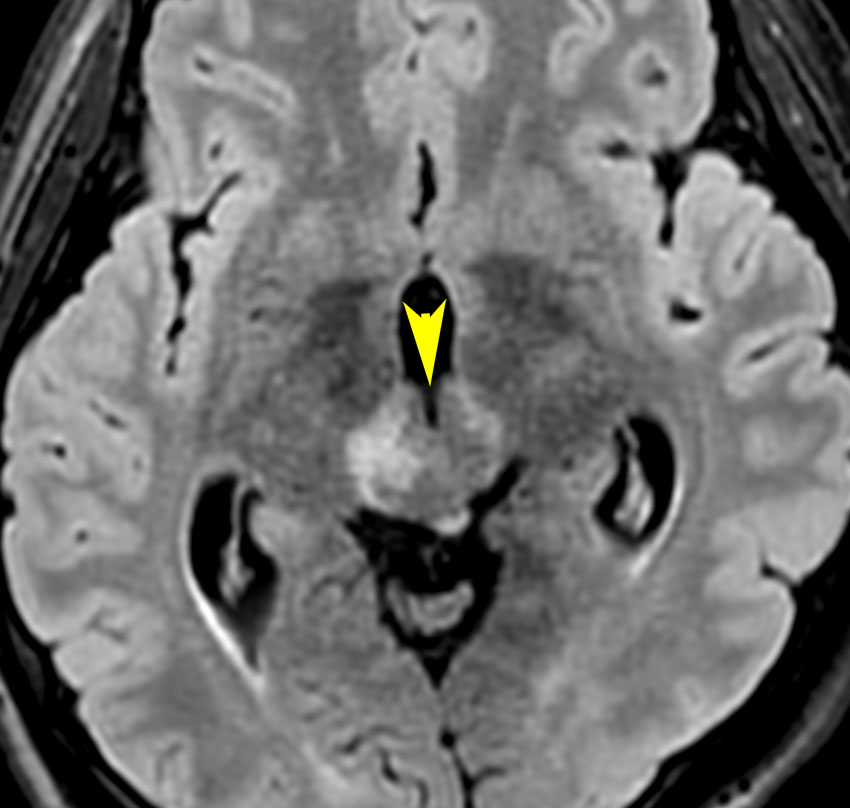

軽度の複視のみで発症した20代前半男性です。右上のように松果体腫瘍の前に割れ目が入るように第3脳室があり,両側視床に浸潤するために軽度の視床浮腫があり,ガドリニウムで強く増強され一部にのう胞があります。これだけでもgeriminomaにかなり特有の所見です。さらに,灰白隆起(矢印)のところに小さな神経下垂体germinoma腫瘍があります (bifocal tumor)。HCGは測定限界以下,AFP 2.5で,水頭症はありません。全ての臨床所見がgerminomaであることを示しています。

生検病理診断をしないでICE化学療法を1コース終えた後の画像です。腫瘍は消失しています。これでgerminomaであることが確認できたので,ICE化学療法を2コース追加して,25.2グレイの全脳室照射をして治療を終了しました。